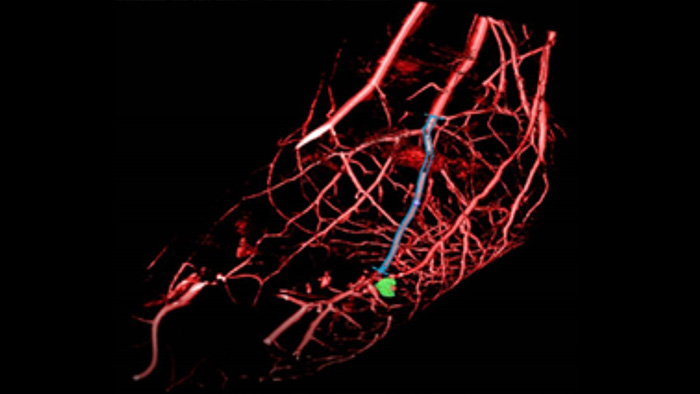

SmartCT Roadmap facilita intervenciones complejas porque proporciona una guía de imágenes en 3D en directo que puede segmentarse para resaltar el vaso y las lesiones objetivo, con lo que ayuda a la navegación a través de estructuras vasculares complejas. Todo ello controlado a través de la pantalla táctil de la mesa.